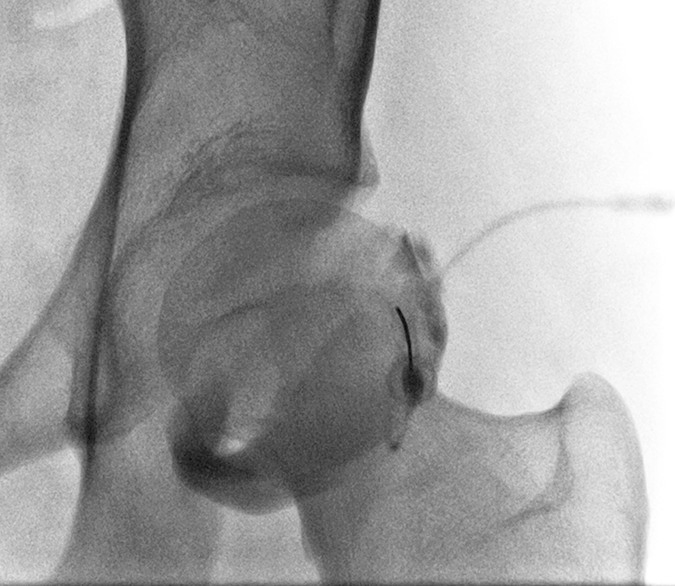

Hip¶

- Hip is internally rotated

- Easiest is lateral edge of bone but can also target lateral cortex and sliding along 2-3mm after making contact for a paracortical approach

- Lateral aspect targeted to avoid neurovascular structures and iliopsoas tendon

- Anterior and paracortical approaches respectively: